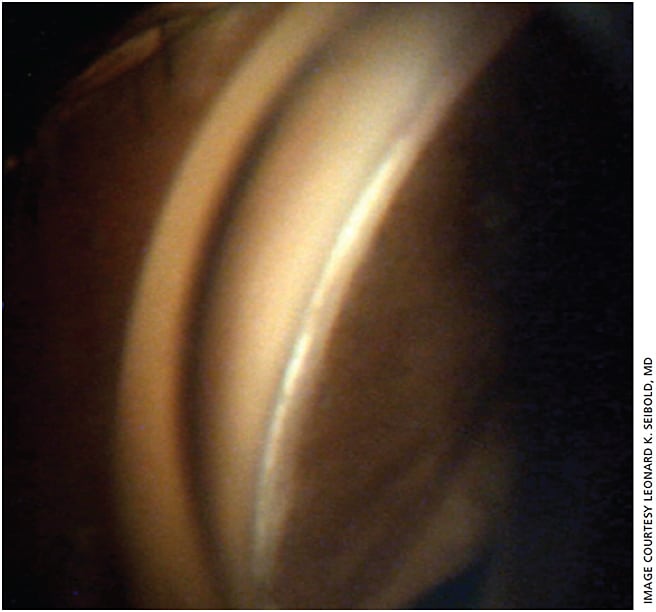

While trabeculectomy and glaucoma drainage devices remain the gold standard for the surgical lowering of intraocular pressure, there has been a recent emergence of surgical techniques designed to lower pressure by re-establishing the natural aqueous humor outflow pathways.1 One such device is the Kahook dual blade (KDB, New World Medical), a single-use goniotomy knife designed to make parallel incisions in the trabecular meshwork (TM). These incisions allow aqueous humor to have free communication between the anterior chamber and distal collector channels (Figure 1). The key feature of the KDB is a ramp on the distal end that allows the TM to be stretched before the KDB’s two blades cleanly remove a wide swath of tissue. The process of elevating the TM on the ramp is essential and represents a significant breakthrough in design efforts.

Once the distal end of the KDB reaches the TM, the surgeon should move the device 2 to 3 clock hours to the right and then enter the canal of Schlemm using the blade’s piercing tip. Some surgeons find it beneficial to direct the distal tip of the KDB up 10° towards Schwalbe’s line prior to piercing the TM. This may help with smoother entry through all TM layers. The heel of the KDB is then settled back on the anterior wall of the canal and advanced from right to left while ensuring the TM is rising over the ramp prior to engaging the dual blades to create parallel incisions.

The treatment is stopped after 2 to 3 clock hours and the same procedure is then repeated from left to right so that a strip of TM is amputated and subsequently removed with irrigation/aspiration or with capsulorhexis forceps (Figures 2 and 3). The viscoelastic is then evacuated and the anterior chamber is inflated to an IOP of 20 to 25 mm Hg (to help push back any refluxed blood) and the wounds are meticulously hydrated for a watertight seal.